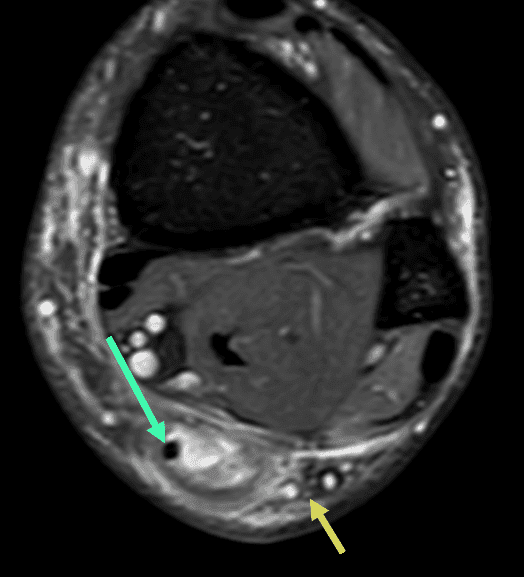

Dans ce cas précis, il existe un tendon plantaire grêle (flèches vertes) qui apparaît continu, épargné par la rupture tedineuse, ce cas de figure est parfois interprété à tort comme une rupture partielle du tendon calcanéen.

Il est important de rechercher la présence d'un tendon plantaire grêle sur le versant médial du tendon calcanéen, car ce tendon accessoire et inconstant peut être prélevé et utilisé dans la reconstruction chirurgicale du tendon calcanéen.

Par ailleurs, notez également la relative proximité du tendon calcanéen avec le nerf sural (flèche jaune) sur le versant latéral du tendon, bien visible en coupe axiale, raison pour laquelle il faut également rechercher des signes de compression nerveuse en cas de volumineux hématome dans les suites d'une rupture tendineuse.

Axial T2 FS